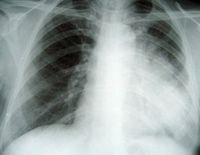

On admission, the patient had a 38°C temperature, 87 beats/min pulse, 130/70 mmHg blood pressure with a 95% oxygen saturation while breathing room air. Respiratory crackles were heard over the left lung field. The rest of the clinical examination was normal. Full blood count, serum chemistries, renal and liver function tests were normal. The screening for human immunodeficiency virus was negative. Sputum cultures were sterile for bacteria, fungi and acid fast bacilli. A bone marrow aspirate and biopsy was normal. A chest X- Ray revealed a left parahilar opacity (Figure 1). Chest CT-scan (Figure 2) revealed a bronchial tumour mass of the left superior lobe classified as T3N0MO: stage IIIA. Bronchoscopy showed an incomplete stenosis by an infiltration of the upper lobe. Biopsies revealed nonspecific inflammation. An extrapericardic left pneumonectomy was performed because of the high suspicion of lung carcinoma. The immuno-histochemical staining showed a polymorphous lymphoid infiltrate expressing CD3+ T cells and CD20+ and CD30+ B cells, and a perivascular infiltrate with extensive tissue necrosis in keeping with angiitis; these findings were consistent with the diagnosis of LYG grade 2 by WHO classification (Figure 3). The patient refused any adjuvant chemotherapy. There was no evidence of any clinical or radiological signs of relapse three years after surgery (Figure 4).

Figure 2. Chest CT-scan showing a bronchial tumour mass of the left superior lobe.